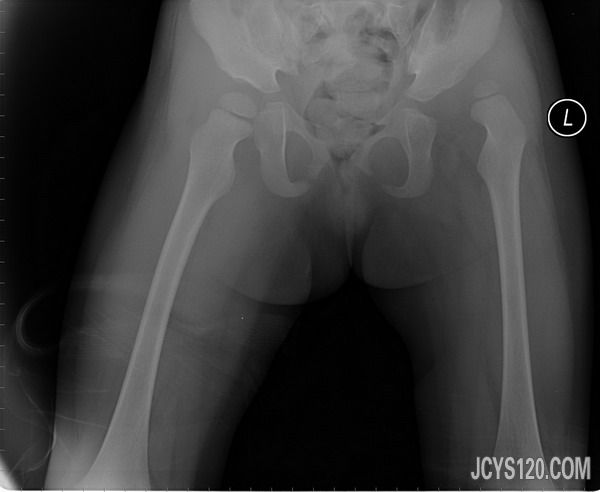

16岁,车祸外伤。因为不是我给她做检查,具体情况我也不好意思问。 阅读全文>

大家看看吧还有治疗价值吗? 阅读全文>